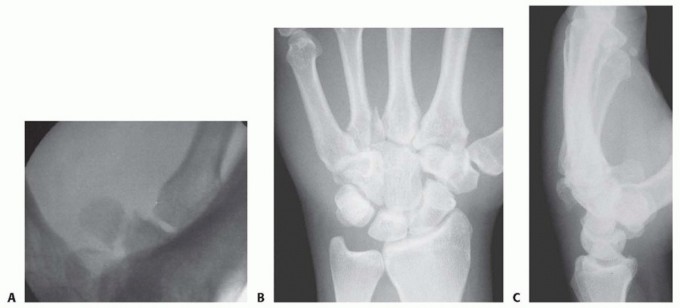

Imaging is the cornerstone of preoperative templating. Routine evaluation begins with high-quality posteroanterior, lateral, and oblique radiographs of the wrist. However, standard views are notoriously inadequate for isolating specific carpal pathology due to osseous overlap. Special radiographic projections are therefore essential. The carpal tunnel view is critical for evaluating the hamate hook and the trapezial ridge. The "papillon view"—a supinated oblique lateral projection with the wrist in radial deviation and the thumb abducted—is highly specific for profiling the hamate hook. Similarly, a 45-degree supinated lateral view optimally visualizes the pisotriquetral articulation.

Despite optimal plain radiography, advanced imaging is frequently required. High-resolution computed tomography (CT) scanning with fine axial, coronal, and sagittal reconstructions has become the gold standard and the imaging modality of choice for complex carpal trauma. CT scans definitively confirm occult fractures, delineate intra-articular comminution, and reveal subtle associated injuries missed on plain films. They allow the surgeon to mentally construct a 3D model of the fracture, facilitating precise preoperative templating of screw trajectories and implant sizes. If dynamic instability is suspected but unconfirmed, an Examination Under Anesthesia (EUA) combined with real-time fluoroscopy (utilizing stress and distraction views) is performed immediately prior to the definitive procedure to finalize the surgical blueprint.

Clinical & Radiographic Imaging Archive